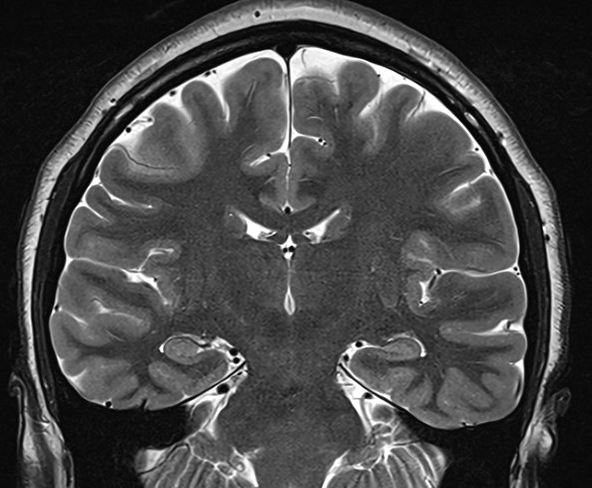

Here are some phantom spike-and-wave discharges from last week. The patient is a young adult.

The above waves appear exclusively while awake and during very light sleep, but none are seen during deeper sleep, including stage II. For what it's worth, there is no history to suggest generalised epilepsy; The history provided by patient and the family suggests right temporal lobe epilepsy of 16 years duration; The patient is entirely unaware of seizures. The father's cousin (mid 50's) has epilepsy, manifest with GTCS without warning, since childhood. The inter-ictal EEG recording is normal. The patient has had 4 recorded seizures lasting 1-3.5 minutes, all of which appear over the right mid-temporal region (T4) on scalp EEG recordings; neither the patient, other patients nor the nursing staff noticed anything when she had these seizures, which were discovered on systematic scrutiny of the EEG recording. The patient and the family think that the seizures are well controlled, but that memory is poor. This likely is a consequence of intermittent amnestic seizures, as these appear on the scalp EEG recordings without a change in the antiseizure medication. The MRI scan of the brain is normal.